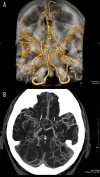

Moyamoya disease is a progressive vasculopathy leading to stenosis of the main intracranial arteries. The incidence of moyamoya disease is high in Asian countries; in Europe and North America, the prevalence of the disease is considerably lower. Clinically, the disease may be of ischaemic, haemorrhagic and epileptic type. Cognitive dysfunction and behavioral disturbance are atypical symptoms of moyamoya disease.Characteristic angiographic features of the disease include stenosis or occlusion of the arteries of the circle of Willis, as well as the development of collateral vasculature. Currently, magnetic resonance angiography and CT angiography with multi-row systems are the main imaging methods of diagnostics of the entire range of vascular changes in moyamoya disease.The most common surgical treatment combines the direct arterial anastomosis between the superficial temporal artery and middle cerebral, and the indirect synangiosis involving placement of vascularised tissue in the brain cortex, in order to promote neoangiogenesis. Due to progressive changes, correct and early diagnosis is of basic significance in selecting patients for surgery, which is the only effective treatment of the disease. An appropriate qualification to surgery should be based on a comprehensive angiographic and imaging evaluation of brain structures.Despite the rare occurrence of moyamoya disease in European population, it should be considered as one of causes of ischaemic or haemorrhagic strokes, especially in young patients.